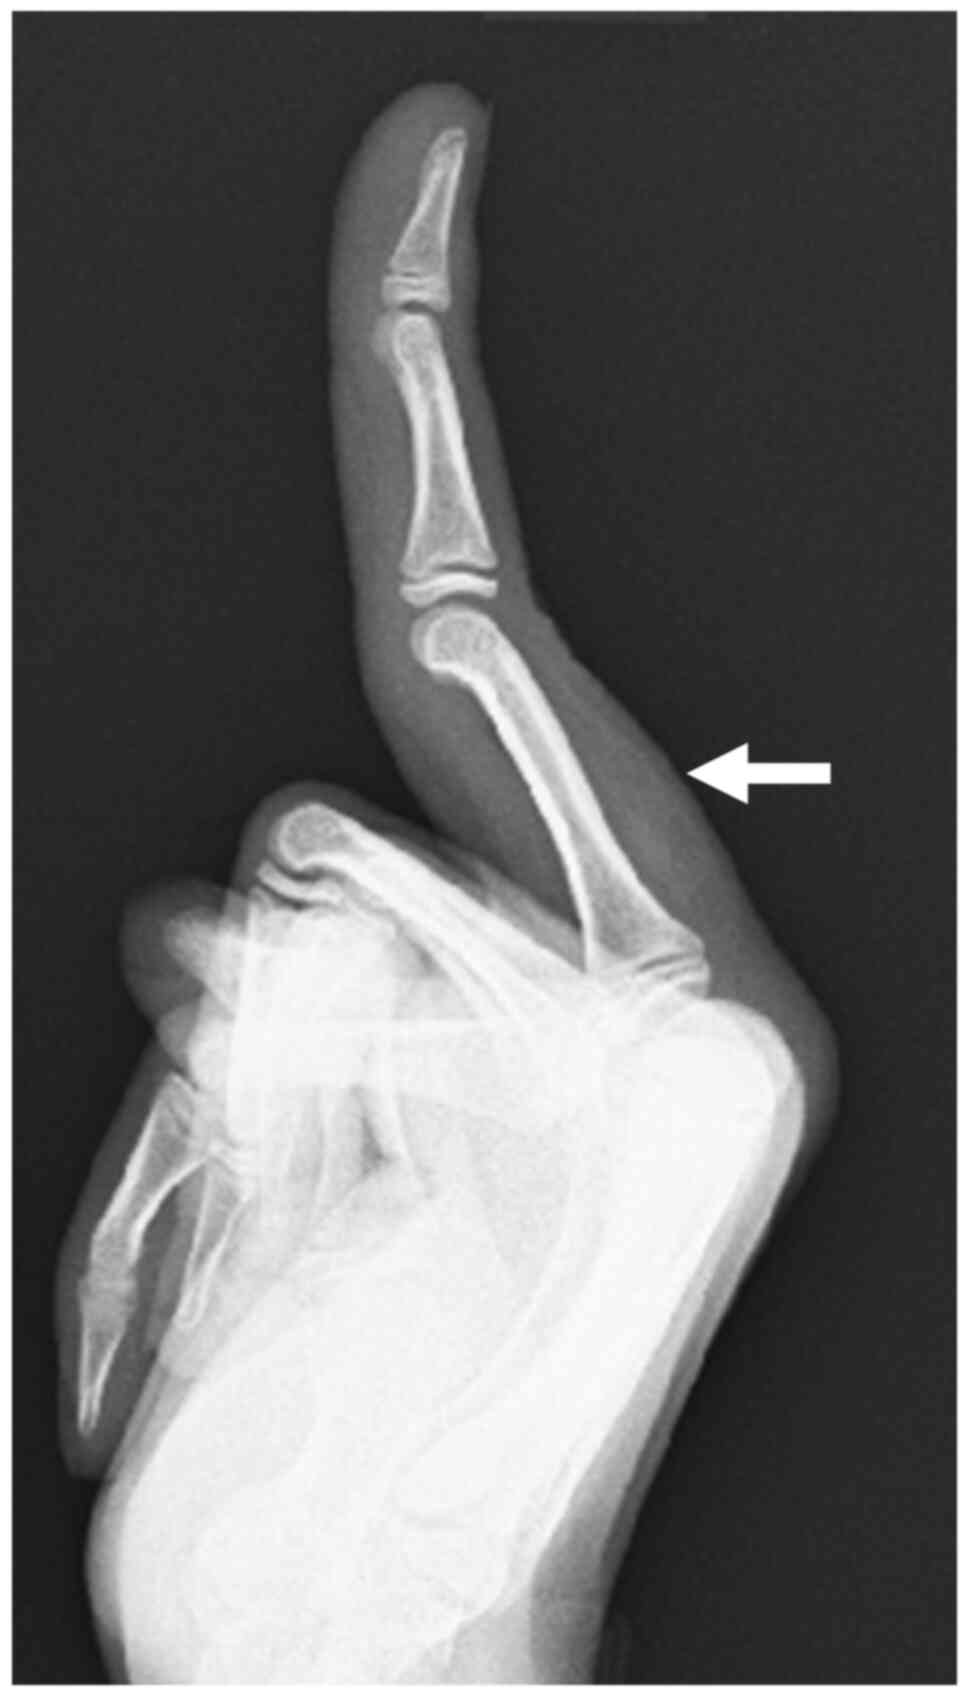

An 11-year-old girl was referred to the Kobe University hospital on March 2017, with a painless mass on the dorsal aspect of the proximal phalanx of her left middle finger, which she had noticed a year ago after catching the finger in a closing door. Clinical examination revealed a well-defined elastic soft mass, measuring 2.5x2 cm, with no associated redness, local heat nor tenderness, and the lesion was mobile without fixation to overlying skin or deeper structures. The functions of the finger including range of motion and sensation were not impaired. A plain radiograph of the left middle finger revealed a soft tissue mass without evidence of a calcification and a bone erosion (Fig. 1). MRI revealed a well-circumscribed 2.5x2x1 cm-sized lesion with heterogeneous signal intensity. On both T1- and T2-weighted images, the lesion showed a predominantly marked hyperintense signal containing linear hypointense regions (Figs. 2 and 3A), and on fat-suppressed short-tau inversion recovery (STIR) sequences, the lesion showed a predominant hypointensity, with linear regions displaying hyperintensity (Fig. 3B). MRI findings suggested a diagnosis of lipoma with non-adipose elements, such as cartilage matrix.

Figure 1

A preoperative radiograph of the left middle finger. White arrow, soft tissue mass without evidence of calcification or bone erosion.